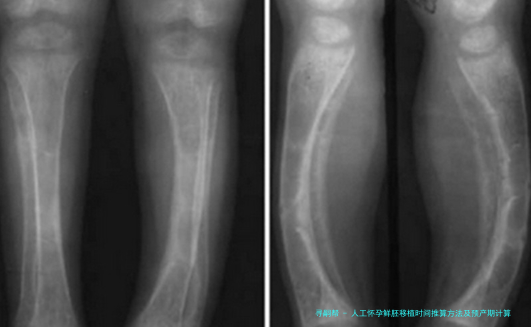

五、B超动态修正机制

孕早期通过量测胚芽长度(CRL)邃密调节孕周:

胚芽长度(mm)对应孕周允许误差范围

3-56周+3天±3天

16-188周+2天±2天

胎心出现时间窗为孕5-6周,晚在自然中妊娠周期一周属正常范围。